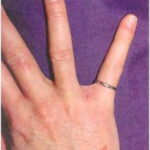

Burrows are the pathognomonic lesions of scabies and are found mostly in the florid, papulovesicular type of sarcoptic acariasis . They are produced by female mites and occur mainly on the palms and plantae, the palmar and lateral aspects of the fingers and toes, the interdigital spaces, the flexor surfaces of the wrists, the nipples of women, the genitals of men, and, to a lesser extent, on the buttocks and axillae. Characteristically, the head is spared, except in newborns and infants . The burrows appear as fine, tortuous, blackish threads a few millimeters long. A vesicle may be visible near the blind end of the burrow. The mite is situated in this vesicle and may be visible as a tiny gray speck by dermatoscopy. Although pathognomonic, the burrow is not the most common lesion seen in scabies. Small, erythematous, often excoriated papules are more frequent . |